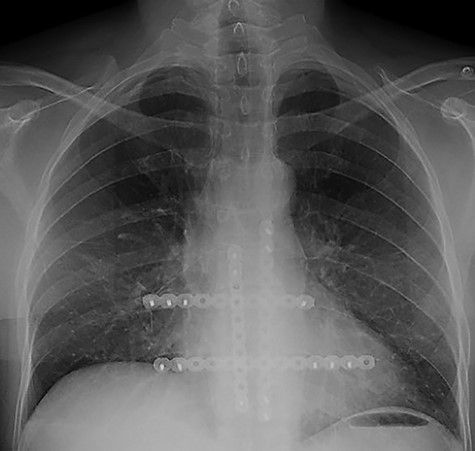

The second case at our institution was a 52-year-old woman with a history of left breast carcinoma treated for which she had undergone left wide local excision and sentinel node biopsy. Due to uncertainty regarding margins, she required a re-resection of her left breast tissue. She completed adjuvant radiotherapy and received maintenance hormonal therapy. She presented 8 months following her radiotherapy with sternal pain and positron emission tomography–computed tomography (PET–CT) imaging demonstrated localized uptake within the sternum (Fig. 3). Biopsy demonstrated proven recurrence of metastatic breast cancer. She was seen in clinic and counselled for partial sternectomy and reconstruction. She underwent partial sternectomy and underwent reconstruction with Synthes® plates. Her post-operative recovery was unremarkable. Post-operative histology was consistent with metastatic breast carcinoma, which was completely excised. The patient made an uncomplicated recovery and was seen in the outpatient clinic with a satisfactory post-operative chest radiograph (Fig. 4).

CT–PET demonstrating increased metabolic activity within the sternal lesion.